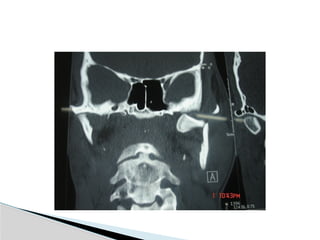

Conventional Radiology

At least 2 views at right angle to each other.

Mandibular series: PA, Lateral oblique or

panoramic, & Towne’s view (projects condyle

below mastoid process).

CT

Significant displacement or dislocation,

mechanical obstruction, mult trauma pt, &

intracapsular fracture.

MRI

St injuries: effusion, visualization of disc.

Imaging

Conventional Radiology At least2 views at right angle to each other. Mandibular series: PA, Lateral oblique or panoramic, & Towne’s view (projects condyle below mastoid process). CT Significant displacement or dislocation, mechanical obstruction, mult trauma pt, & intracapsular fracture. MRI St injuries: effusion, visualization of disc. Imaging